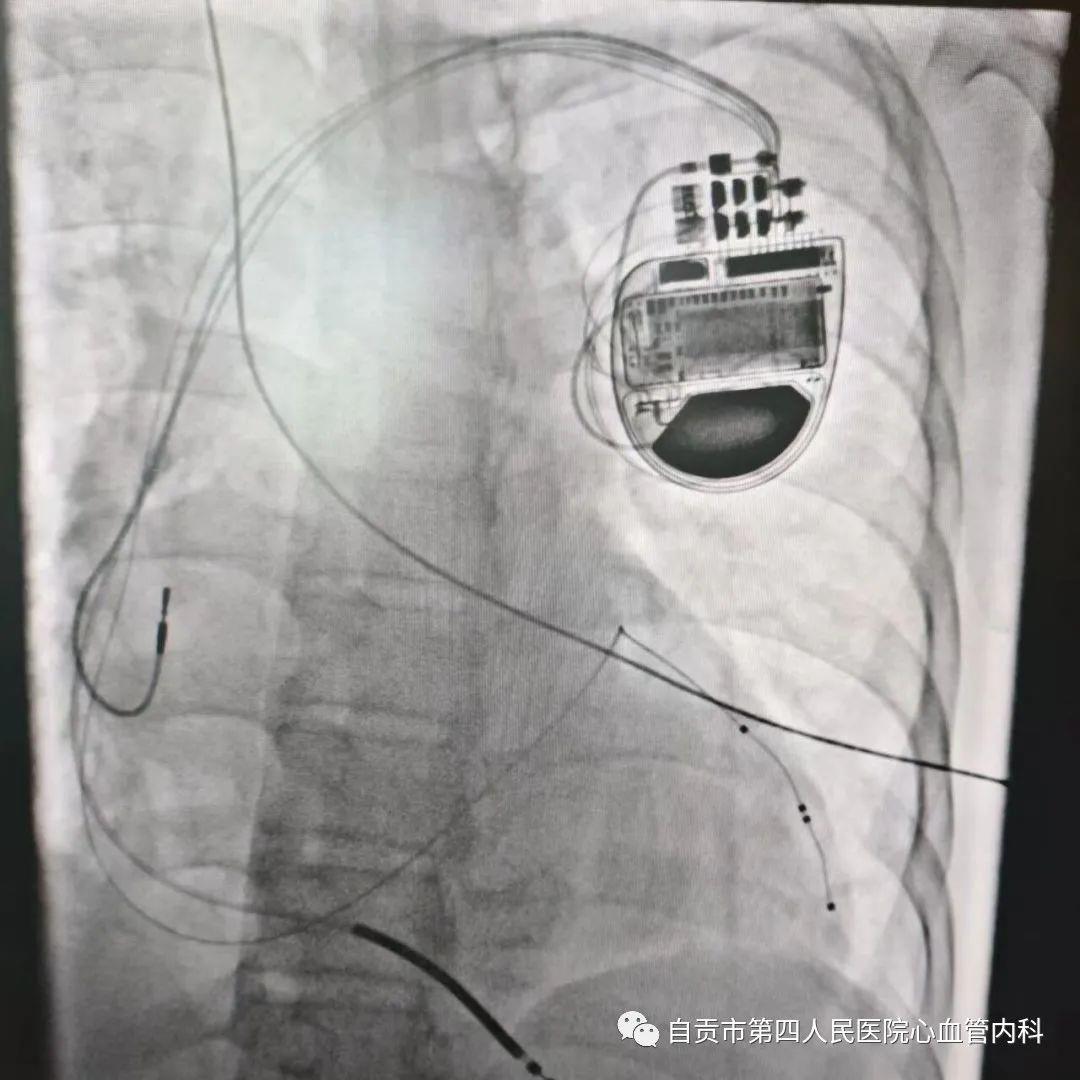

2023年7月16日,自贡市第四人民医院心血管内科介入团队在罗裕主任领导下荣幸邀请到上海同济大学附属东方医院大咖浦介麟教授来院授课,并在教授指导下成功为一位扩张型心肌病患者顺利植入了一个三腔起搏器(CRT-D),让患者衰竭的心脏重获新生,该手术技术难度大,省内仅有较大的心脏中心开展,手术的成功标志着我院心内科在心脏起搏治疗领域又迈上了新台阶。

患者系53岁中年男性,反复心累、气促8年余,多次在我科住院治疗,经正规抗心衰治疗后患者心衰症状仍反复,彩超提示全心扩大,左心扩大明显(LV:64mm、LA:47mm),心功能明显下降(EF:25%),心电图提示窦性心律伴完全性左束支传导阻滞,提示左右心室收缩不同步。患者说:“现在自己生活都成困难呀!需要有人照顾,轻微活动就气喘吁吁,我出院后也是按照医生的指导规律服用药物,但病情仍越发加重,反复住院,效果越来越差,对人生也充满了绝望”。 ![]() 术前心电图提示:窦性心律,完全性左束支传导阻滞 ![]() 术前心脏彩超 入院后罗裕主任组织科室医生反复讨论病情,调整治疗方案。根据患者病情,药物治疗较局限,目前最有治疗希望的是行三腔起搏器植入术,该患者符合三腔起搏器植入适应症,决定为患者施行CRT-D植入术。 术前心血管内科医务人员做好充分术前准备,告知患者及家属手术的过程,术后预后及注意事项,让患者家属充分了解手术相关知识。 术中浦教授主刀,在心内科团队的密切合作下,手术顺利完成,术后患者恢复良好。 ![]() ![]() ![]() 目前心衰的治疗方案主要以药物治疗为主,但是随着病情的进展,心衰患者常反复发作及住院,部分心衰患者单纯药物治疗效果较差,致残、致死率较高,三腔起搏器的植入可使心房和心室同步,左右心室同步收缩和舒张,从而增加心脏泵血功能,明显改善患者心衰症状,提高生活质量,减少住院率,降低死亡率,同时带有除颤器植入,可预防大心脏、心衰患者并发恶性心律失常致心脏骤停的风险,是心力衰竭治疗史上一个里程碑式的突破。 三腔起搏器(心脏再同步除颤器)是目前治疗心衰最有效的方法之一,但该手术技术难度大,手术操作要求高,传统起搏器的植入主要通过静脉穿刺输送两根电极分别植入右心房、右心室即可,三腔起搏器第三根电极要求植入的位置是左心室,常规通过冠状静脉窦逆行至心脏侧静脉植入左室电极,极大的增加手术难度及风险,全国在心脏大中心开展稍多,省内地市级医院鲜有开展,该项手术的成功开展为心衰患者带来新的希望,同时标志着我院起搏技术及心衰治疗水平的走在全省前列。 浦教授还分享了心律失常晕厥的治疗和诊断方法,浦教授在讲课中强调对晕厥患者进行危险分层,尤其是不明原因晕厥,采用短期危险和长期危险的分层方法;并推荐了基于危险分层的处理策略,让我们受益匪浅。 ![]() ![]() ![]() 自贡市第四人民医院心血管内科专业成立于1974年,于2003年独立建科,经过六十多年的发展,我科目前已成为集医疗、教学和科研为一体的综合心血管内科诊疗中心,总体医疗和科研水平在市内处于先进地位。科室拥有高素质的医疗队伍,参与多项国家级课题及省市级科研项目,拥有三间现代化的介入导管室,两台进口大型C臂机,主动脉球囊反搏泵、电生理导航系统、心内电生理检查+射频消融治疗仪、心脏彩超、血管内超声系统、冠脉旋磨系统、震波球囊技术、临时起搏器、除颤仪、呼吸机、中央监护系统等一大批高精尖设备。 我院是自贡市首家一次性通过“胸痛中心”认证的医疗单位,是自贡地区唯一 中国心血管疾病基层医师培训示范中心,是国家临床医学研究中心协同网络成员单位;我科技术实力雄厚,在自贡地区首家开展经导管主动脉瓣置换术(TAVR),是“国家心脏瓣膜介入中心”建设单位,“国家标准化房颤中心”建设单位;目前能独立开展经导管主动脉瓣置换术(TAVR)、冠脉内旋磨技术、冠脉震波球囊(Shockwave)技术及无导线起搏器植入术等高精尖心脏介入技术 ;并在市内较早开展冠脉内超声检测(IVUS)、冠脉血流储备分数(FFR)等精确评估冠脉结构和功能病变的技术手段,以及房颤的“三维射频消融”及“一站式”服务(射频消融+左心耳封堵术),为心血管疾病患者提供高质量的诊疗服务。 目前科室常规开展冠心病的介入治疗,包括:冠状动脉造影,血栓抽吸技术,冠脉支架植入术,IVUS,FFR,冠脉内旋磨技,震波球囊等国内顶尖技术。 结构性心脏病的介入治疗,包括:经导管主动脉瓣置换术(TAVR),房间隔缺损、室间隔缺损、动脉导管未闭,卵圆孔未闭,各种动静脉瘘的介入封堵术;肺动脉狭窄,主动脉缩窄支架植入术;肺动脉瓣,二尖瓣狭窄的球囊扩张术;肥厚梗阻性心肌病化学消融术;肺动脉高压的心导管检查等。 心律失常介入治疗,包括:临时起搏器、永久心脏起搏器、ICD、CRT-D植入术;阵发性室上性心动过速、房扑、房速、房颤、特发性室早、特发性室速的三维射频消融;心房颤动的“一站式”服务(射频消融+左心耳封堵术)等。心脏病介入治疗领域处于省内先进水平。 ![]() ![]() 浦介麟,联邦德国医学搏士,教授,博士生导师,我国心律失常领域著名专家,留学欧美12年。曾任阜外心血管病医院心律失常诊治中心23B病区主任;院、所病理与生理实验中心主任;院、所学术委员会委员兼内科组秘书。1994以优秀博士论文获联邦德国心脏电生理学博士学位,在从事心律失常介入治疗的同时深入基础研究领域。1994-1998年在美国纽约哥伦比亚大学做博士后期间,完成美国国立卫生研究院系列研究题。2002年回国后从事心电生理和起搏临床和研究工作,创建心律失常基础研究室;负责973等国家级课题6项,参加6项;2005年筹建了阜外医院病理与生理实验中心并兼任主任,为院内外有关研究提供技术平台支持。 现任上海同济大学附属东方医院心脏医学部执行主任。擅长复杂危重心律失常的诊治,完成介入手术5千余例,包括起搏器,除颤器(ICD),三腔起搏器(CRT),三腔起搏和除颤器(CRT-D)等。负责973等国家级课题13项,发表论文140余篇,其中SCI论文60余篇。获国家科技进步二等奖等国内外奖项12项。担任中国心脏联盟晕厥学会副主任委员,中国生物医学工程学会心律分会常委、心脏起搏和遗传性心律失常工作委员会副主任,中华医学会心电生理与起搏分会基础研究学组副组长等学术兼职;《中华心血管病杂志》、《中华心律失常学杂志》、《中国循环杂志》、《疑难病杂志》等专业杂志副主编和编委。 ![]() 易勇,硕士,副主任医师,为四川省医学会心血管专委会委员、四川省康复医学会心血管分会委员、四川省心脏瓣膜联盟常委、四川省医疗事故鉴定专家库专家、自贡市医学会心血管专委会委员、自贡市心血管质量控制专家组成员。先后在专业期刊发表论文多篇,获市级引进新技术三等奖2项。擅长复杂冠脉介入治疗和高龄患者起搏器安置术。 ![]() 罗裕,医学博士,主任医师,硕士研究生导师,现任自贡市第四人民医院心血管内科主任,是中国介入心脏病大会,东方会,长城会等国内顶级大会主席团成员,多次在上述大会进行复杂高危手术直播演示。为韩国峨山医学中心访问学者,日本札幌心脏病中心高级访问学者。 擅长各种复杂高危冠脉的介入治疗;并在心律失常,心力衰竭,高血压,晕厥,成人先心病及心脏瓣膜疾病等方面亦积累了丰富的经验。发表文章50余篇,其中第一及通讯作者文章21篇,SCI收录10篇;主持了多项上海市卫健委、江西省卫健委、浦东新区课题;主编了《冠状动脉瘤样扩张:从发病机制到临床实践》,参编了《现代心血管病诊疗》、《分子心脏病学》等著作。获国家实用新型专利1项。 ![]() ![]() ![]()